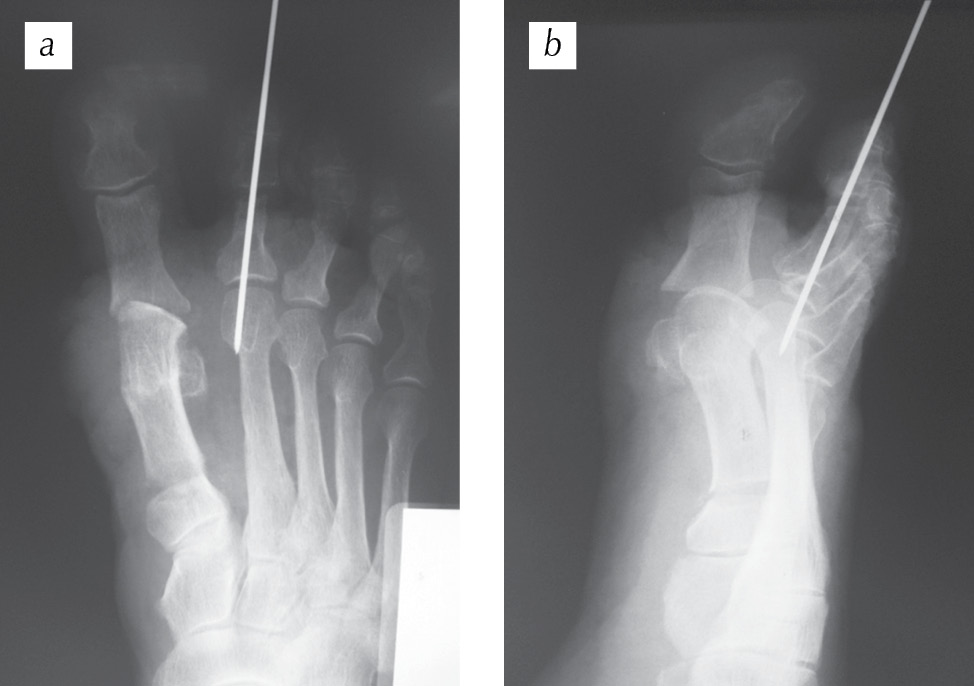

На рис. 4 представлены рентгенограммы пациентки в двух проекциях сразу после оперативного лечения. Угол вальгусного отклонения I пальца, образованный осями I плюсневой кости и проксимальной фаланги I пальца, равен 8° при норме 8–16°. Межфаланговый угол I пальца, образованный осями проксимальной и дистальной фаланг I пальца, равен 0° при норме 0–8°. Угол варусного отклонения I плюсневой кости, образованный осями I и II плюсневых костей, равен 13° при норме 5–14°. Угол наклона суставной поверхности головки I плюсневой кости, образованный осью I плюсневой кости и осью, проведенной перпендикулярно линии, соединяющей края суставной поверхности головки I плюсневой кости, равен 10° при норме 3–10°. Угол наклона суставной поверхности основной фаланги к ее оси, образованный проксимальной фалангой I пальца и перпендикуляром к плоскости суставной поверхности этой же фаланги, равен 0° при норме 0–5°. Угол наклона суставной поверхности медиального плюснеклиновидного сустава, определяемый как угол между линией данного сустава и перпендикуляром к тангете медиального края медиальной клиновидной кости, равен 20° при норме 0–20°.

Рис. 4. Рентгенограммы переднего отдела правой стопы пациентки Е. сразу после оперативного лечения: а — прямая проекция; b — косая (3/4) проекция (пояснения см. в тексте)

Fig. 4. Radiographs of the anterior part of the right foot of patient E. immediately after the surgery: а — straight projection; b — oblique (3/4) projection (see the text for explanations)

Послеоперационный период протекал без осложнений, назначали обезболивающую, антикоагулянтную, антибактериальная терапию, выполняли перевязки. Швы сняты на 12-е сутки. Больная передвигалась при помощи костылей без нагрузки на правую нижнюю конечность. Через 3 нед. после оперативного лечения выполнен рентгенологический контроль в двух проекциях: положение спицы удовлетворительное, определяется место остеотомии основания I плюсневой кости (рис. 5).

Рис. 5. Этапный рентгенологический контроль через 3 нед. после операции: а — прямая проекция; b — косая (3/4) проекция (пояснения см. в тексте)

Fig. 5. Stage x-ray control 3 weeks after the operation: а — direct projection; b — oblique (3/4) projection (see the text for explanations)